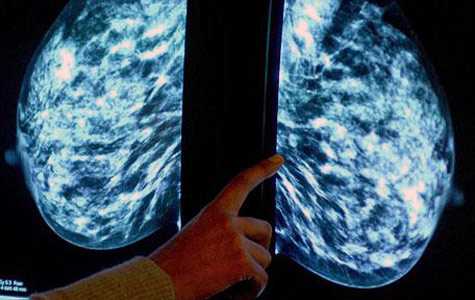

Các kỹ thuật viên đang tiến hành kiểm tra một khối u ở ngực có dấu hiệu bị ung thư vú.